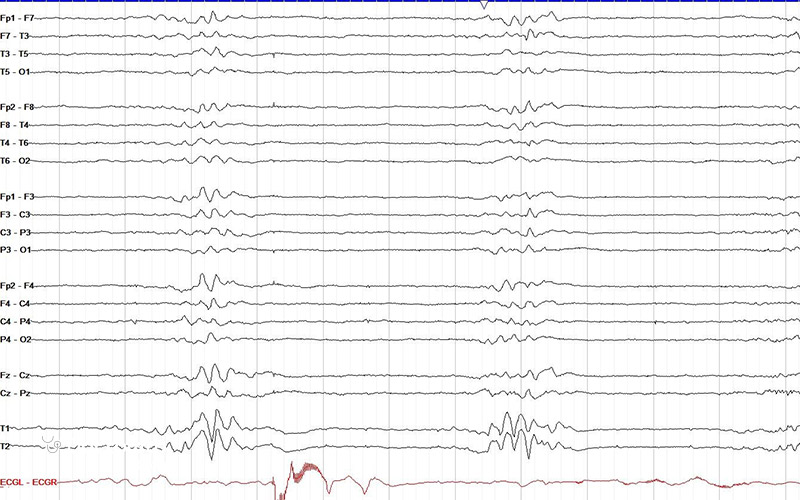

نوار مغزی به زبان ساده آزمایشی است که فعالیت الکتریکی مغز را بررسی میکند و برای تشخیص ناهنجاریها و تغییرات امواج مغزی به کار میرود. این آزمایش که با نام الکتروانسفالوگرافی یا EEG هم شناخته میشود، با استفاده از دیسکهای فلزی کوچکی به نام الکترود انجام میشود که روی پوست سر قرار میگیرند.

الکترودها فعالیت الکتریکی مغز را دریافت کرده و سیگنالها را به یک کامپیوتر منتقل میکنند تا ثبت و تحلیل شوند. نتیجه نوار مغزی به صورت الگوهای موجدار با قلهها و درهها نمایش داده میشود. پزشک با بررسی این الگوها میتواند به سرعت تشخیص دهد که آیا فعالیت مغز طبیعی است یا نشانهای از اختلال وجود دارد.

پس از آماده شدن نتایج، شما یک جلسه پیگیری با پزشک خود خواهید داشت تا آنها الگوهای امواج مغزی ثبت شده در آزمایش را بررسی کنند. با این حال گاهی ممکن است بخواهید خودتان نگاهی به برگه نوار مغز بیندازید و بدانید چه چیزی را نشان میدهد. به زبان خیلی ساده میتوان گفت:

- خطوط سریع و کوچک نشان دهنده فعال و بیدار بودن مغز هستند.

- خطوط کند و بزرگ نشان دهنده آرام بودن مغز و خواب بودن هستند.

- خطوط غیرمعمول یا تیز و الگوهای غیرطبیعی ممکن است نشان دهنده مشکلی مثل تشنج یا اختلال مغزی باشند.

تفسیر نوار مغز (EEG) به معنای بررسی و تحلیل الگوهای فعالیت الکتریکی مغز است تا اختلالات عصبی و عملکرد مغزی شناسایی شود. پزشک با مشاهده ریتمها، امواج و تغییرات غیرطبیعی EEG میتواند محل و نوع اختلال را مشخص کند. پزشکان نوار مغز را بر اساس نوع موجهای مختلف تفسیر میکنند که عبارتند از:

- موج آلفا (۸ تا ۱۲ هرتز) در زمان بیداری همراه با آرامش دیده میشود (همچون زمانی که چشمها بسته است اما فرد بیدار است).

- موج بتا (۱۲ تا ۳۰ هرتز) در زمان بیداری و هنگام فعالیت ذهنی و تمرکز ظاهر میشود.

- موج تتا (۴ تا ۸ هرتز) نشان دهنده حالت آرامش عمیق یا خواب سبک است.

- موج دلتا (کمتر از ۴ هرتز) نشان دهنده خواب عمیق است. وجود بیش از حد آن در بیداری میتواند نشانهای از آسیب مغزی یا اختلالات جدی باشد.